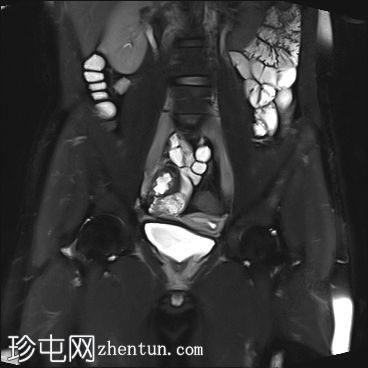

矢状位

T2

9.jpg

MRI图像显示子宫和睾丸。子宫内膜腔开口于前列腺尿道。

患者有双侧隐睾病史。CT和MRI图像显示发育良好的子宫和两个睾丸,均位于盆腔内。子宫内膜腔开口于前列腺尿道。